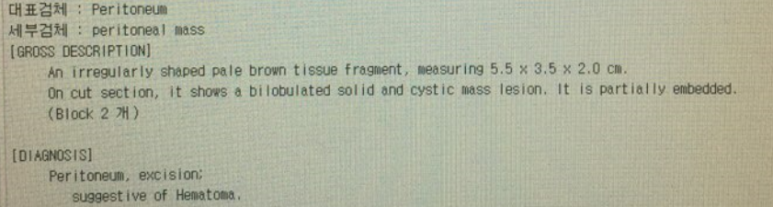

대학병원에서 CT시행 판독

; r/o lymphangioma, neurogenic tumor with cystic change, mucinous cystadenoma

조직결과; 혈종